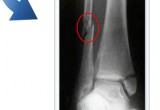

BonesFracture.com also features the different ways to determine fracture, such as through X-rays or bone scans which are procedurally taken when bone fracture symptoms are found during physical examination. In some cases, physicians recommend the use of MRI or CT scans to see clearer images of the bones, or to detect even hairline fractures.